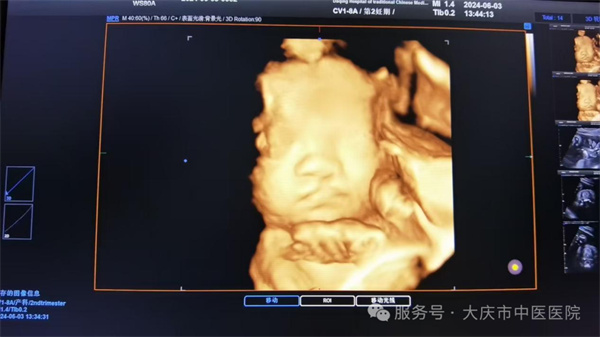

近日,大庆市中医医院超声医学科通过四维彩超筛查,为一位准妈妈做出了及时准确的胎儿发育健康提示。该孕妇为第二次妊娠,曾孕育一健康女孩,现孕23周,在超声医学科进行胎儿系统筛查时,当日值班医生,超声医学科副主任王双艳,经过一番认真细致的检查,发现胎儿存在左侧三度唇裂伴左侧牙槽突裂,其余胎儿结构未见异常。随即向孕妇及家属详细介绍唇腭裂的类型、程度及可能对胎儿出生后的影响,如影响外貌、进食、发音等,同时说明不同程度唇腭裂的治疗方法和预后情况,让孕妇对胎儿病情有全面、客观的认识。最后孕妇决定继续妊娠,足月剖产后证实了产前的诊断。截至目前超声医学科已诊断各型唇腭裂5例,均得到产后证实。

大庆市中医医院四维彩超设备,为三星WS80A彩超诊断系统,具有极高的清晰度和分辨率。能360°全方位立体呈现胎儿表面畸形、内脏畸形和头面部畸形及宫内发育情况,如胎儿孕周、体重大小,预产期的估测,脐带血流及胎儿宫内缺氧的评估等,还有子宫动脉的超声评估,是应用于胎儿产前筛查、及完整记录胎儿宫内高清动态的先进超声设备。超声医学科以规范化的胎儿系统筛查标准服务于广大孕产妇,严格做到标准、规范、细致、认真。在此也提醒准妈妈们,要重视产前超声检查,以超声之“眼”,为“好孕”护航。